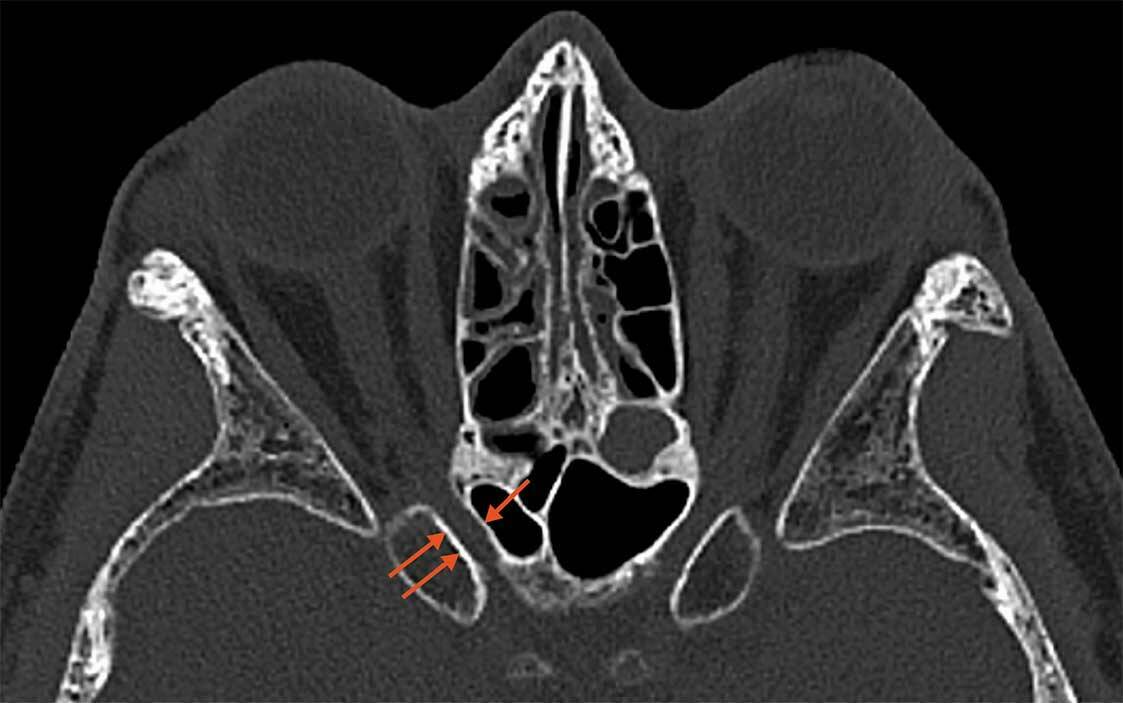

Figure 2. Patiente de 26 ans présentant une baisse d’acuité visuelle avec un décollement séreux rétinien hémorragique visible à l’OCT (A, tête de flèche). Les temps tardifs de l’angiographie à la fluorescéine ne montrent aucune diffusion (B) et la rupture de la membrane de Bruch est hypofluorescente sur le temps tardif de l’angiographie au vert d’indocyanine (C). L’OCT-A segmentée sur la rétine externe ne montre aucun signal vasculaire (D).